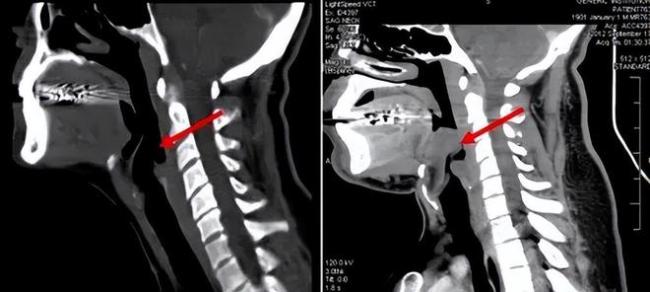

会厌,位于气管的上方,这个部位可以随着吞咽的动作而进行上下扇动。

这么说可能很难理解,直白点说,当人在吃饭吞咽时,会厌会像盖子一样盖住咽喉入口,防止食物进入喉腔或气管引起呛咳;而人在呼吸时,会厌又会向上开放,以保证气流能顺利进入气管。

会厌一旦发炎,就会不断肿胀,严重时可能会肿胀成球状,这时气道便会封闭,人也就无法呼吸。

这也是急性会厌炎如此凶险的根本原因,所以发病后没有及时得到诊疗,患者会在短时间内窒息,死亡率很高。